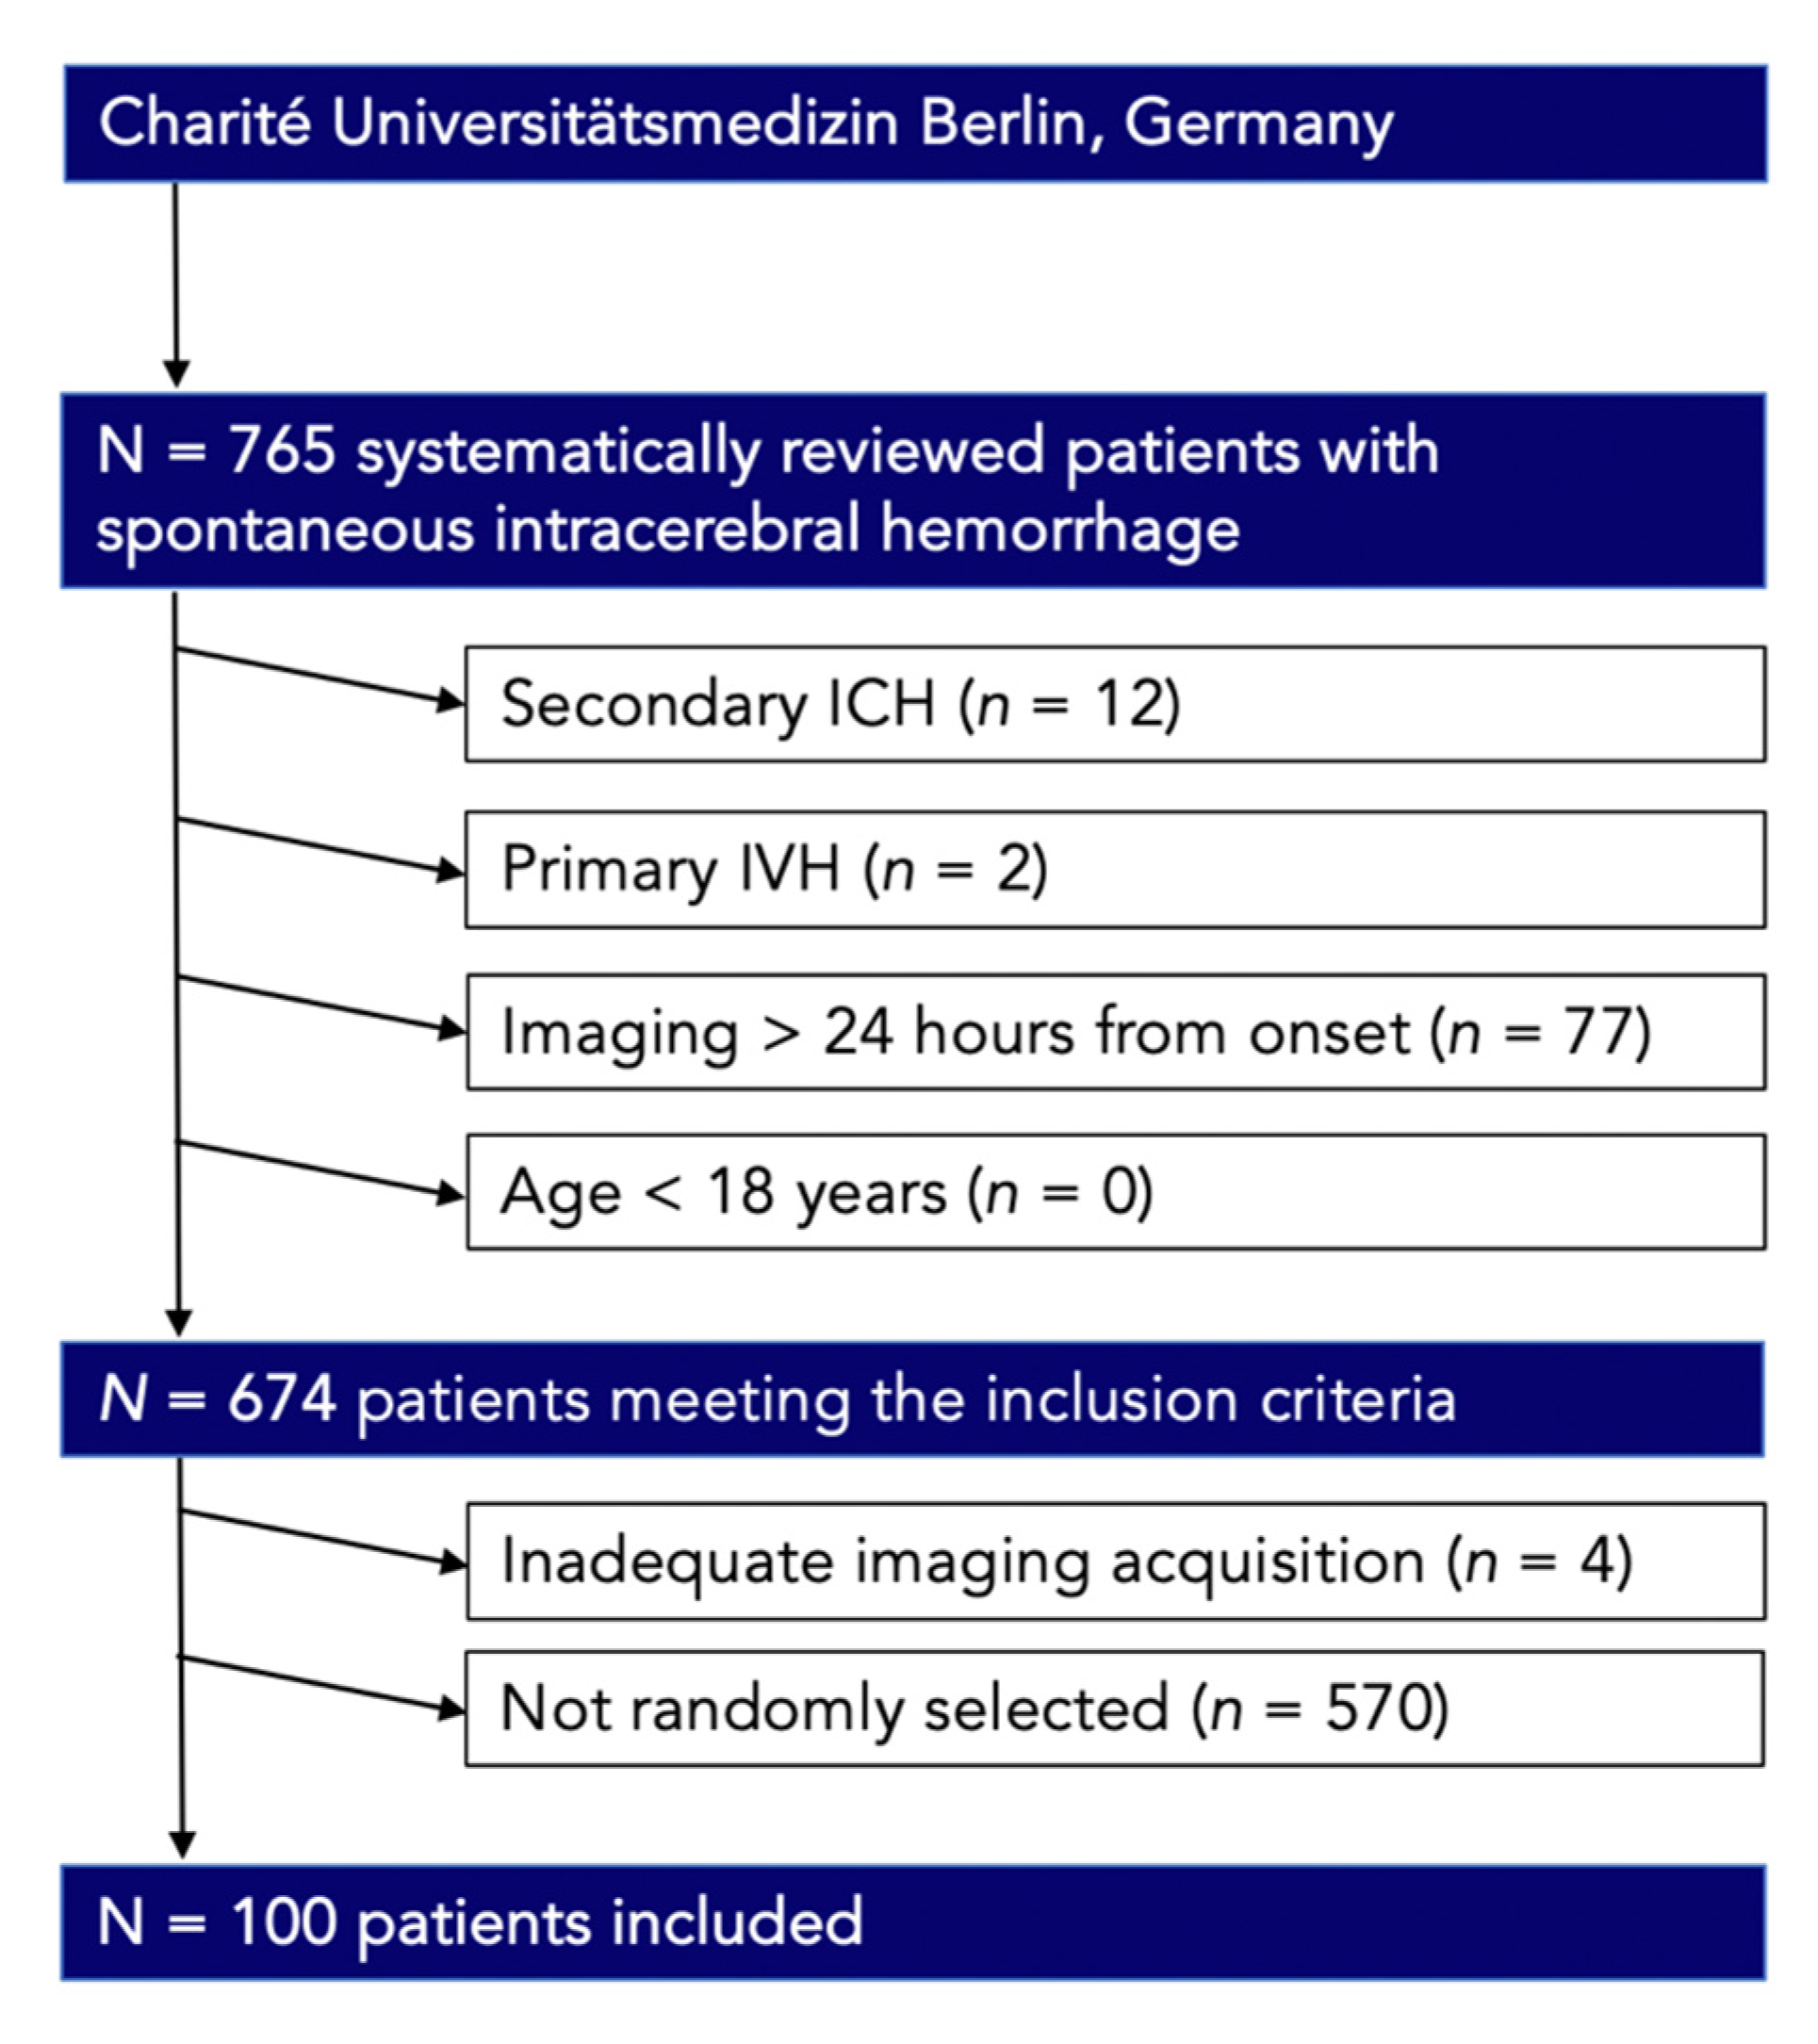

2.1. Study Population